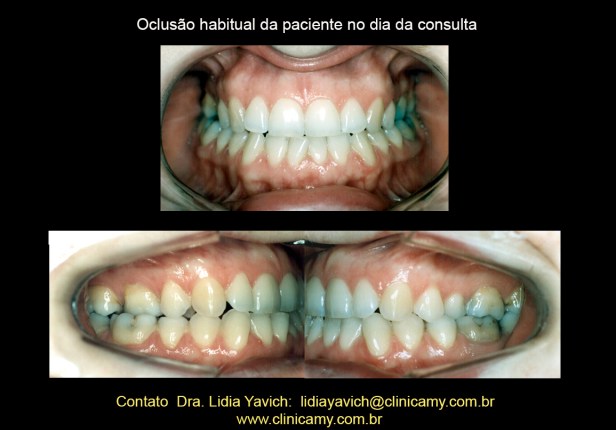

Oclusão habitual da paciente no dia da consulta.

Oclusão habitual da paciente no dia da consulta.